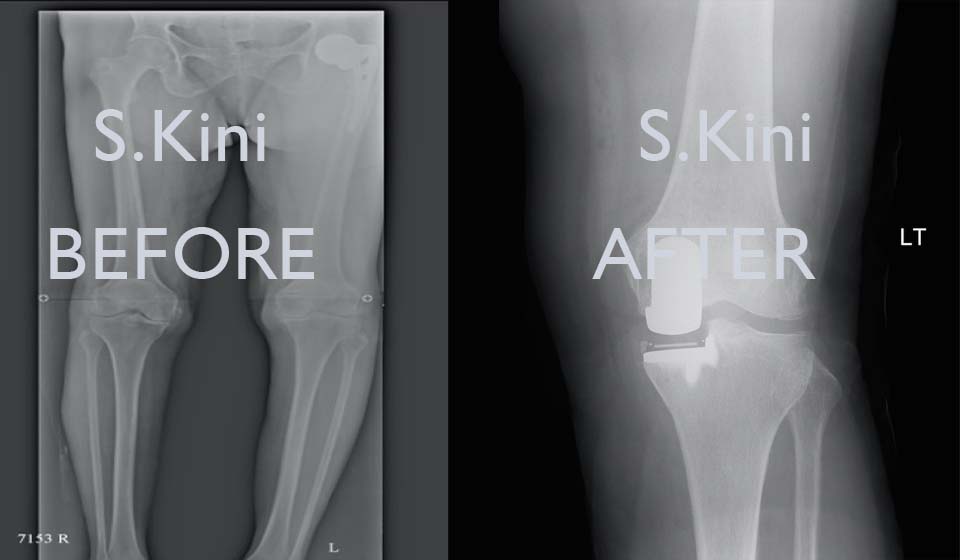

Knee osteotomy is a surgical procedure that may be recommended if you have arthritis damage in just one area of your knee. The procedure involves removing or adding a wedge of bone to your upper shinbone (tibia) or lower thighbone (femur) to help shift your body weight off the damaged portion of your knee joint.

Knee osteotomy is most commonly performed on people who may be considered too young for a total knee replacement. Total knee replacements wear out much more quickly in people younger than 55 than in people older than 70